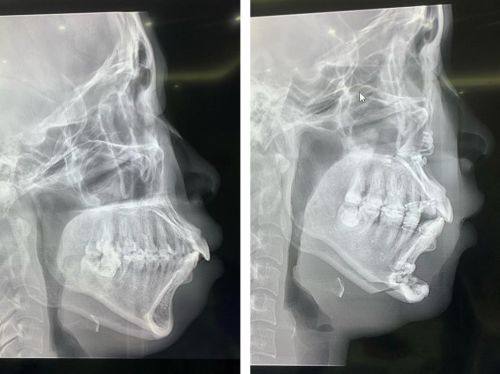

地包天矫正:拥有专精矫正团队,结合口腔全方面检查数据制定个性化矫正方案,能有效改善地包天问题,调整面部咬合与轮廓线条。

唐山星范医美朝阳道医疗美容门诊部地包天矫正:12800元起

张先生:地包天矫正

“我从小就有地包天的问题,一直特别自卑,不敢在人多的地方大笑。后来了解到唐山星范是唐山地包天矫正的推荐医院,就抱着试试的心态过来询问。医生给我做了全方面的口腔检查,制定了适合我的隐形矫正方案,每次复诊都耐心调整牙套,解答我的疑问。现在矫正快一年了,牙齿已经整齐了特别多,面部线条也变得协调自然,终于能自信地露出笑容了。”